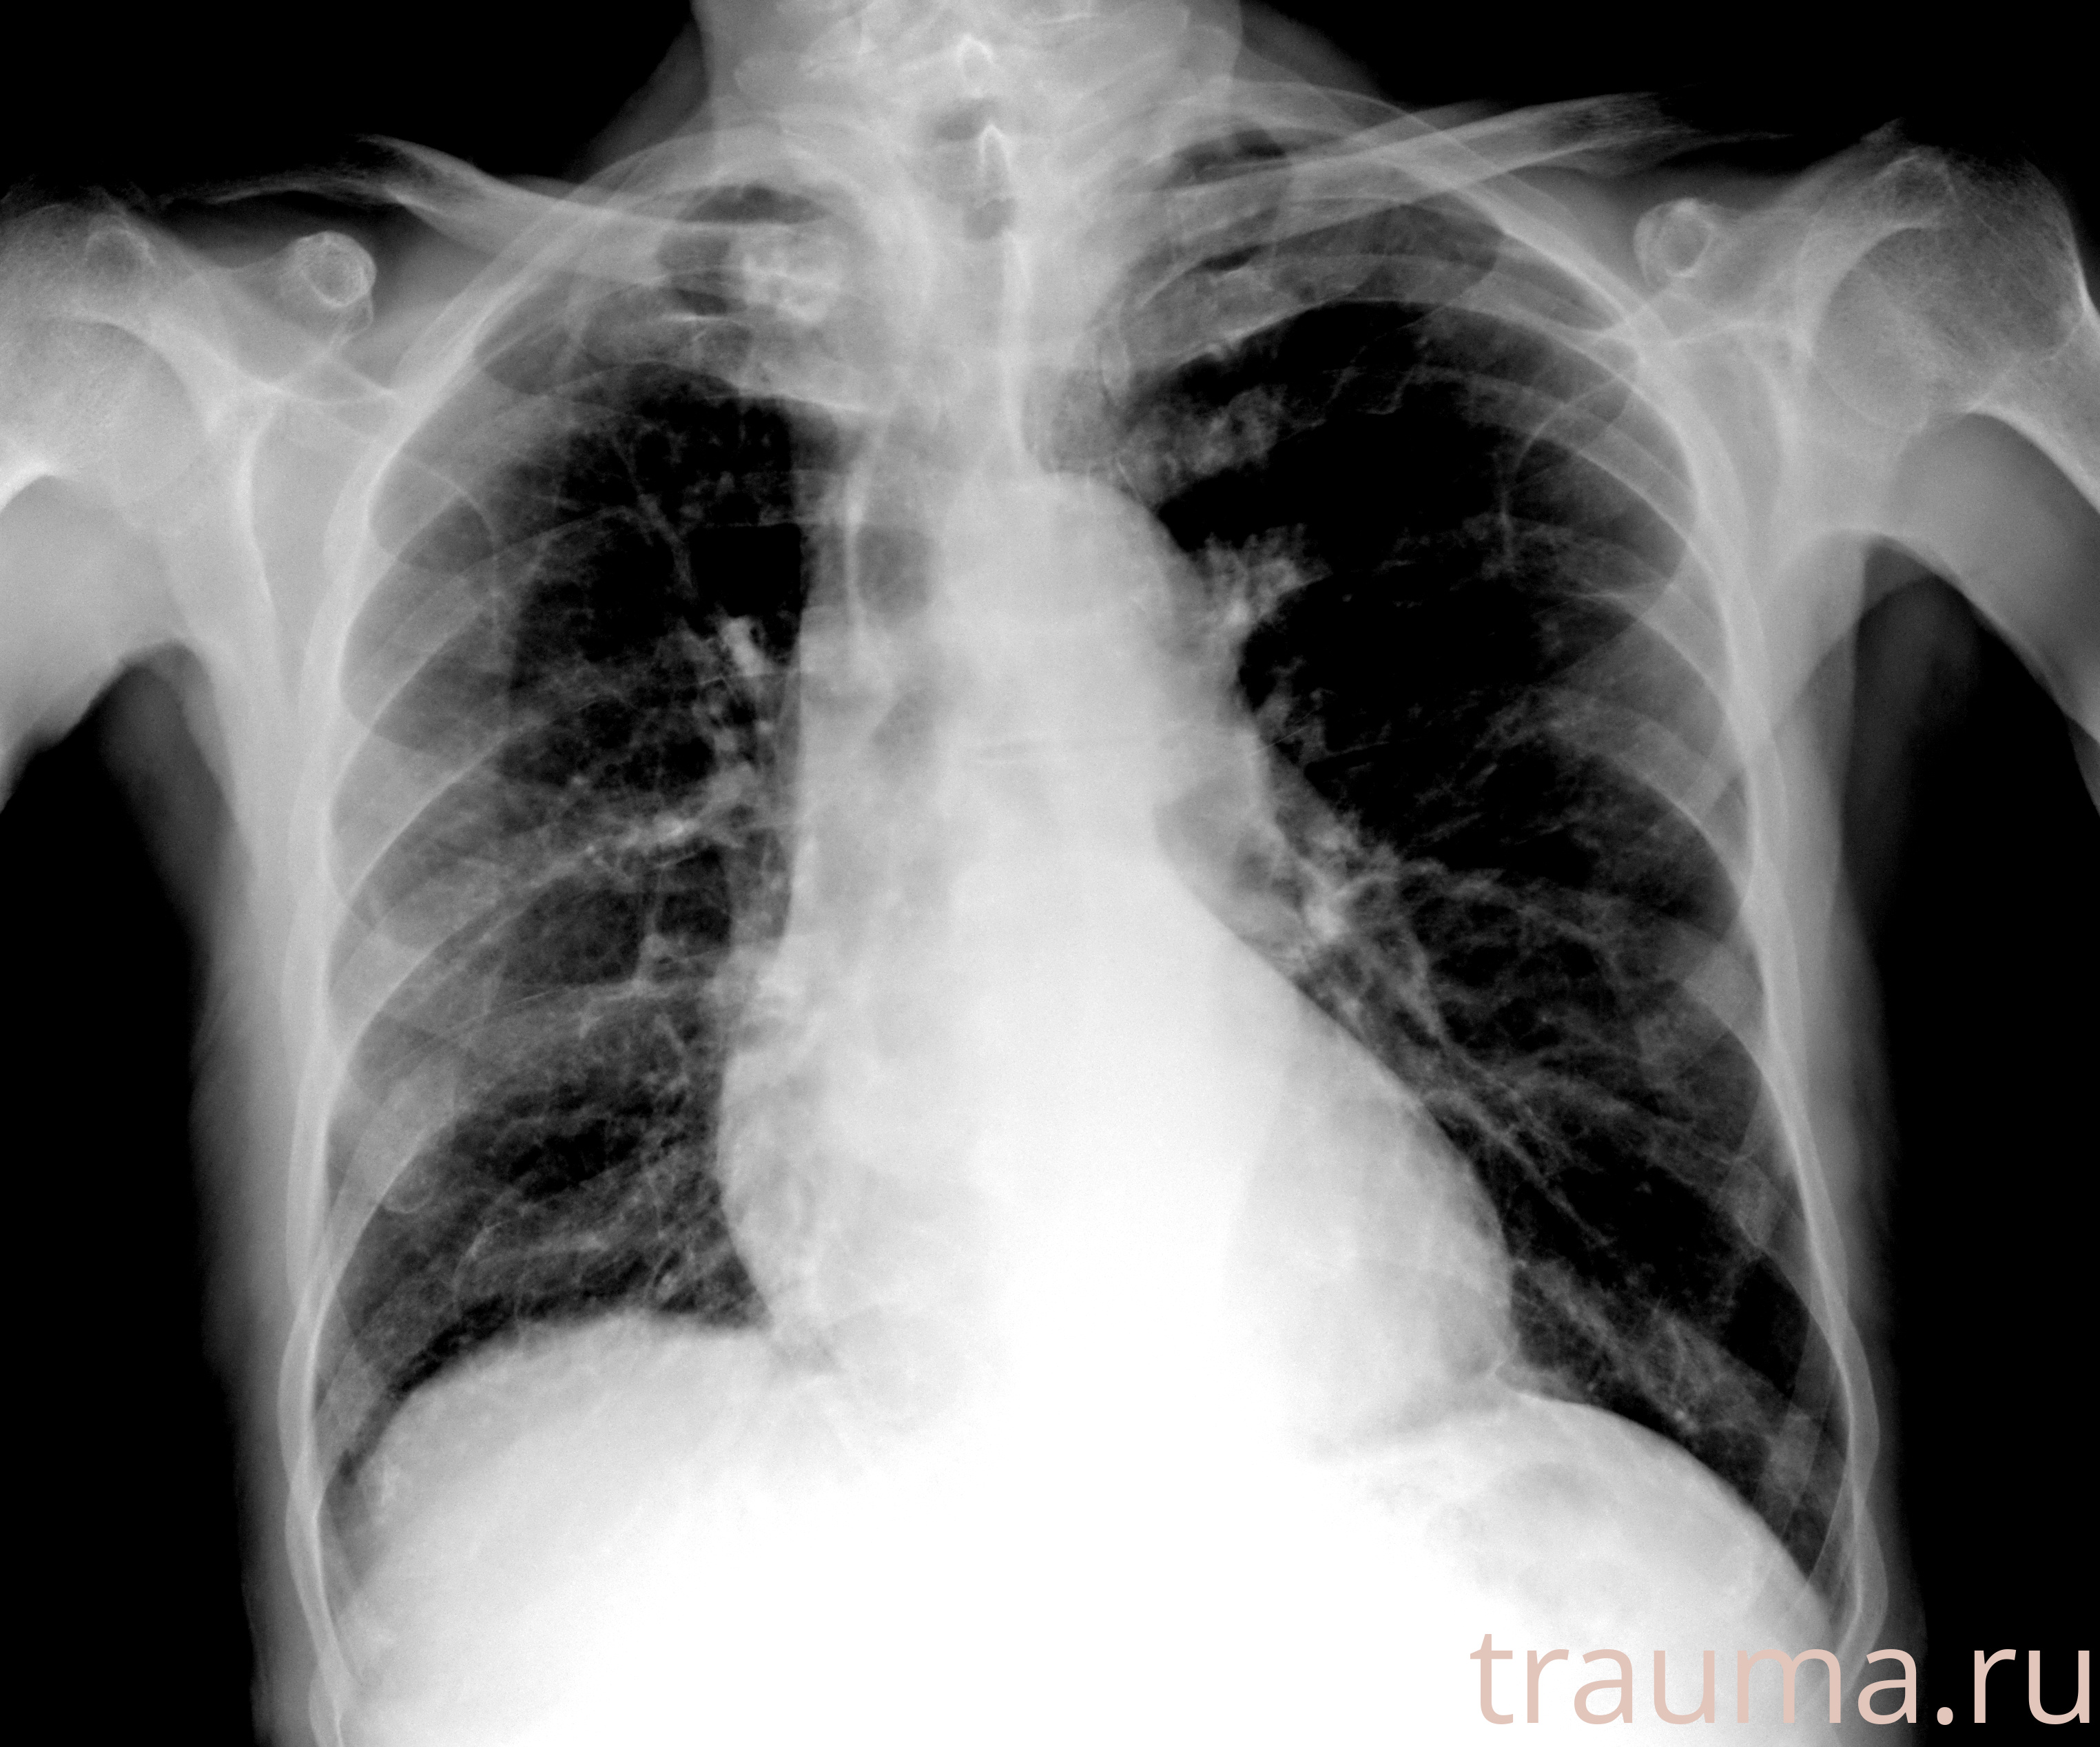

Рентгенограммы

Рентген на дому: по вашему адресу приезжает врач-рентгенолог, травматолог-ортопед с мобильным рентгеновским аппаратом, проводит диагностику травмы или заболевания, делает необходимые рентгенограммы, дает рекомендации по дальнейшему лечению. Получить качественные снимки в домашних условиях возможно благодаря уникальной методике, разработанной МосРентген Центром для института  Склифосовского